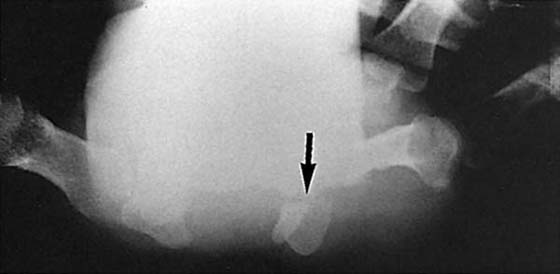

Arthrography

Arthrography is used to evaluate the integrity of the carpal ligaments and triangular fibrocartilage (TFC) (Fig. 13-16, online). The examination involves injecting dye into the radiocarpal, radioulnar, and midcarpal compartments, so it must be performed carefully.1 The injection of contrast material into the joint can highlight intra-articular soft tissue structures such as ligaments and fibrocartilaginous structures.16 Communication of dye between the compartments of the wrist can be caused by a clinically unimportant perforation and does not necessarily indicate pathology.17 Thus, the test results must be correlated with the clinical examination and interpreted with a great deal of caution. The examination is invasive but can be administered with minimal discomfort to the patient.

Figure 13-16 Arthrography of the wrist. A, This normal arthrogram was obtained after injecting dye into the radiocarpal joint. No leakage into the midcarpal joint or radioulnar joint is seen. B, Leakage into the distal radioulnar joint (arrow) is evident in this patient. Clinical correlation is needed to accurately interpret this finding.

The role of arthrography had declined because of the excellent visualization of intra-articular structures by MRI.18,19 Arthrography has also been found to be only 60% accurate in detecting tears in the triangular fibrocartilage complex (TFCC), scapholunate ligament, or lunotriquetral ligament.20 Arthrography is currently used as a complement to MRI and CT to enhance the diagnostic accuracy.21